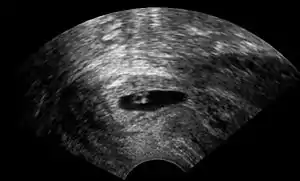

| Vaginal ultrasonography of a cervical pregnancy at a gestational age of 5 weeks. See image below for details of the visible structures.[1] | |

The diagnosis is made in asymptomatic pregnant women either by inspection seeing a bluish discolored cervix or, more commonly, by obstetric ultrasonography. A typical non-specific symptom is vaginal bleeding during pregnancy. Ultrasound will show the location of the gestational sac in the cervix, while the uterine cavity is "empty". Cervical pregnancy can be confused with a miscarriage when pregnancy tissue is passing through the cervix.